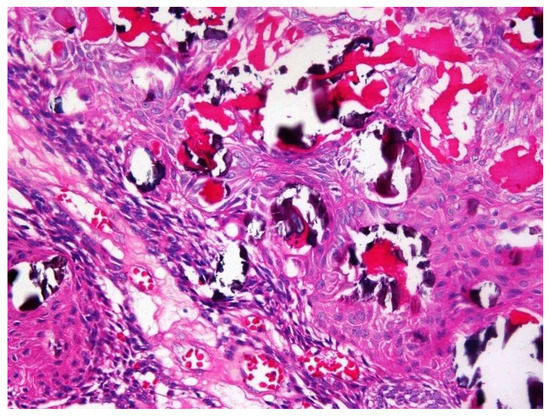

Simple bone cysts (SBC) are pseudocysts occurring less commonly in the maxillofacial region. The uncertain and unclear etiopathogenesis led to numerous synonyms to refer this particular cyst. These cysts are devoid of an epithelial lining and are usually empty or contain blood or [...] Read more.

Simple bone cysts (SBC) are pseudocysts occurring less commonly in the maxillofacial region. The uncertain and unclear etiopathogenesis led to numerous synonyms to refer this particular cyst. These cysts are devoid of an epithelial lining and are usually empty or contain blood or straw-colored fluid. In jaws initially it mimics a periapical cyst and later can lead to cortical bone expansion warranting for radical approach, which is seldom required. SBC is predominantly diagnosed in first two decades of life. Here we report a case of solitary bone cyst mimicking a periapical cyst of a mandibular molar in a 37-year-old patient. Full article